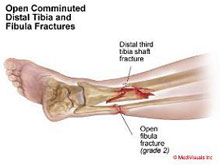

La región de la pierna engloba las diáfisis o zonas centrales de la tibia y el peroné. Son las fracturas de huesos largos (fémur, tibia, húmero, cúbito y radio) más frecuentes en el adulto y pueden producirse por un impacto directo (accidentes de tráfico, caídas desde gran altura, deportes de contacto o de motor) o por un mecanismo indirecto (torsión de la pierna en deportes de salto o sobrecarga repetida en bailarines y reclutas). El tratamiento varía en función del desplazamiento y el grado de afectación de la musculatura y piel circundante. El avance en las técnicas quirúrgicas ha permitido, cuando la indicación lo requiere, el empleo de una cirugía mínimamente invasiva que permite reparar grandes fracturas a través de mínimas heridas disminuyendo la agresión al tejido y favoreciendo la rápida incorporación a la actividad diaria.